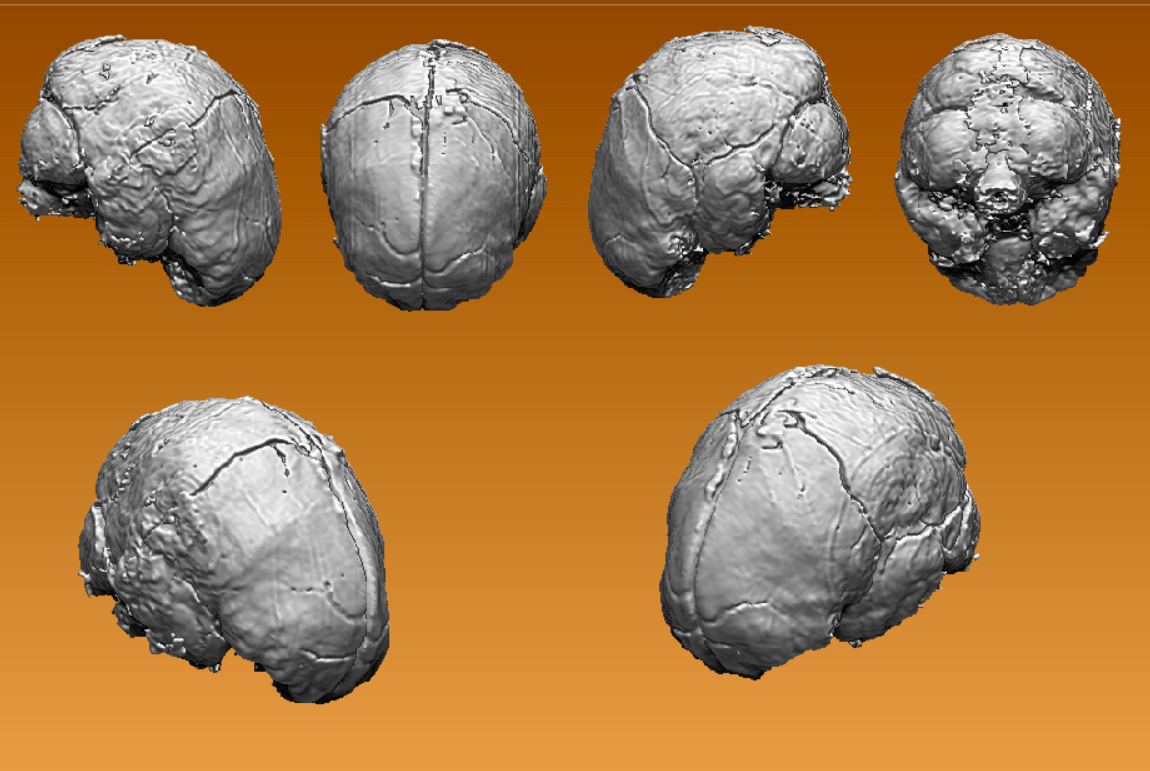

With the brain model in ZBrush, the next step was making it 3D print-friendly. Every scan file comes with cleanup work like removing artifacts and smoothing out rough areas.

Things to consider included:

1) Final size of the 3D print

2) Detail level of gyri and sulci (those brain wrinkles)

3) Printer bed limits and whether to split the brain into parts

4) Detachable or permanently fused parts

5) Other print limitations discovered along the way